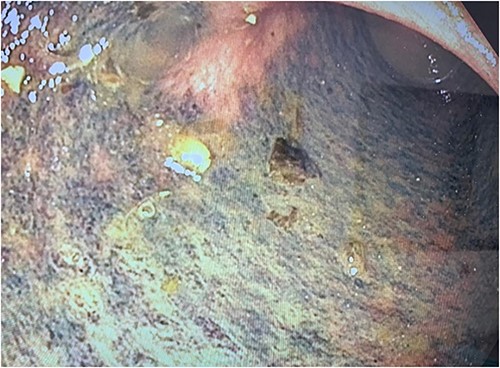

Intraoperative photo demonstrating a cord-like structure crossing over the rectosigmoid colon. This was thought to be the ureter with stent in situ.

The colon was visibly dilated and macroscopically appeared viable with no external evidence of ischemia; however, on-table flexible sigmoidoscopy revealed an acute angulation at the rectosigmoid junction with evidence of mucosal ischemia distally (Fig. 3). Immediately adjacent to this area of obstruction extraluminally was the transplanted ureter with stent in situ. On discussion with her transplant surgeon, a de-functioning loop colostomy was created.

Photograph of the mucosal ischaemic changes in the part of the colon distal to the area of compression by the cord-like structure (presumably the stented ureter).